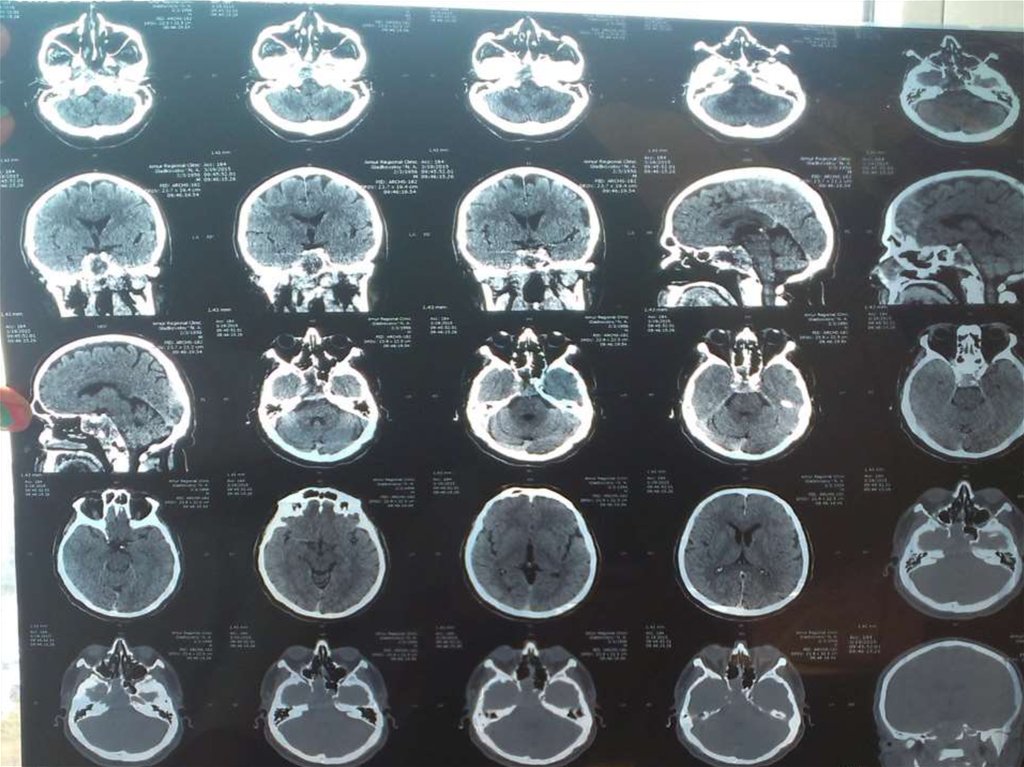

9. Дополнительные методы обследования.

Компьютерная томограмма ОНП от 19.03.15:

признаки объёмного образования основной

пазухи, прорастающего в боковую стенку справа с

распространением в полость черепа.

Магнитно-резонансная томография

мозга с контрастом от 7.04.2015:

Опухоль основания черепа, больше

данных за петрокливальную

менингиому.